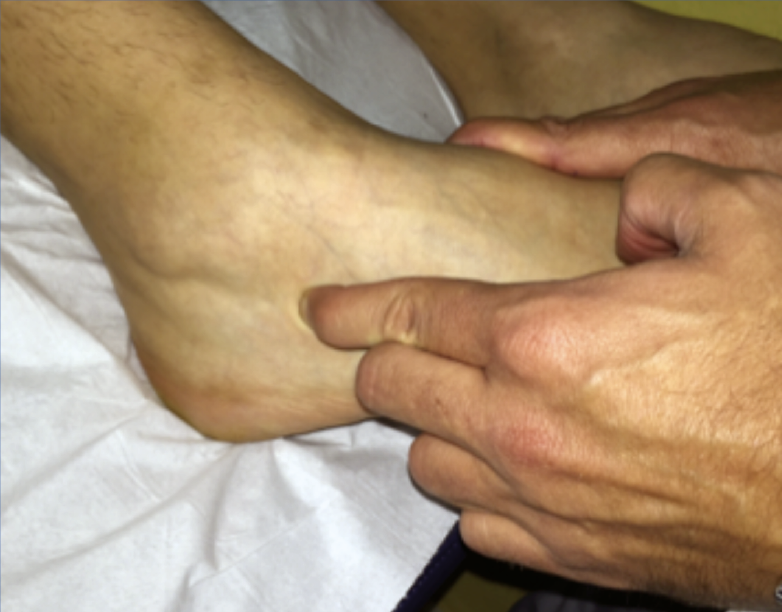

Figura 5. Maniobra de inestabilidad subtalar. Con el retropié en inversión y una ligera rotación interna del medio/antepié, realizamos apertura del seno del tarso y palpamos observando si aparecen síntomas cuando comparamos con el contralateral. Si hay dolor y aumento del tejido en el seno del tarso en el contexto de inestabilidad mecánica de tobillo podríamos estar ante una inestabilidad subtalar combinada.

Inestabilidad subtalar

- Aumento de la inversión y de la rotación interna.

- Exploración superponible con la inestabilidad tibioastragalina; de hecho, suelen coexistir y su diagnóstico diferencial es difícil (Figura 5).

- Plantear infiltración anestésica en el síndrome del seno del tarso (si mejora globalmente, pensar en una lesión al menos parcial del ligamento interóseo ± ligamento cervical).